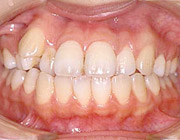

矯正治療前

矯正治療後(完成型)